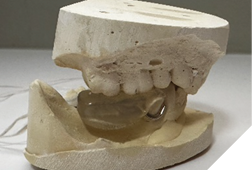

Finally, a cast lower partial denture (Shaw Lab, Kingston, Ontario) was fabricated (Fig. 5ABC). The occlusal design followed anterior/cuspid guidance (Fig. 6). After insertion and minor adjustments, the patient reported comfort and complete resolution of joint symptoms.

Fig. 5A

Fig. 5B

Fig. 5C